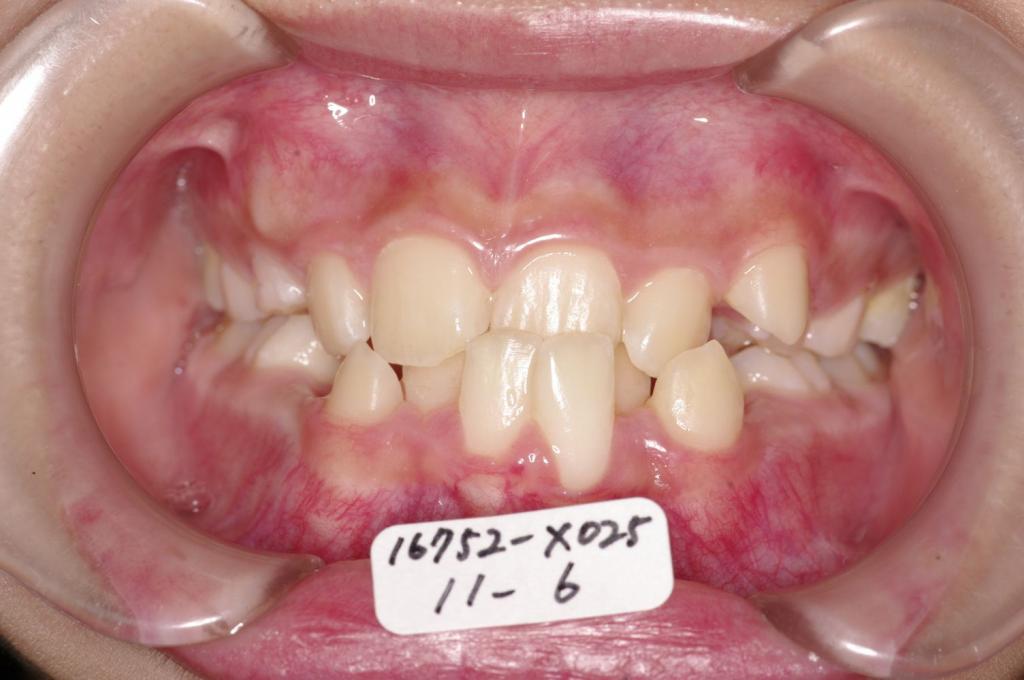

子供の矯正治療

(治療期間、治療前後写真、治療方法、費用)WORKS

下記の実績データをクリックして頂くと「性別」、「治療開始年齢」、「治療終了年齢」、「治療方法(矯正治療装置写真含む)」、「治療終了までの費用」など、詳細な矯正治療データをご覧頂けます。